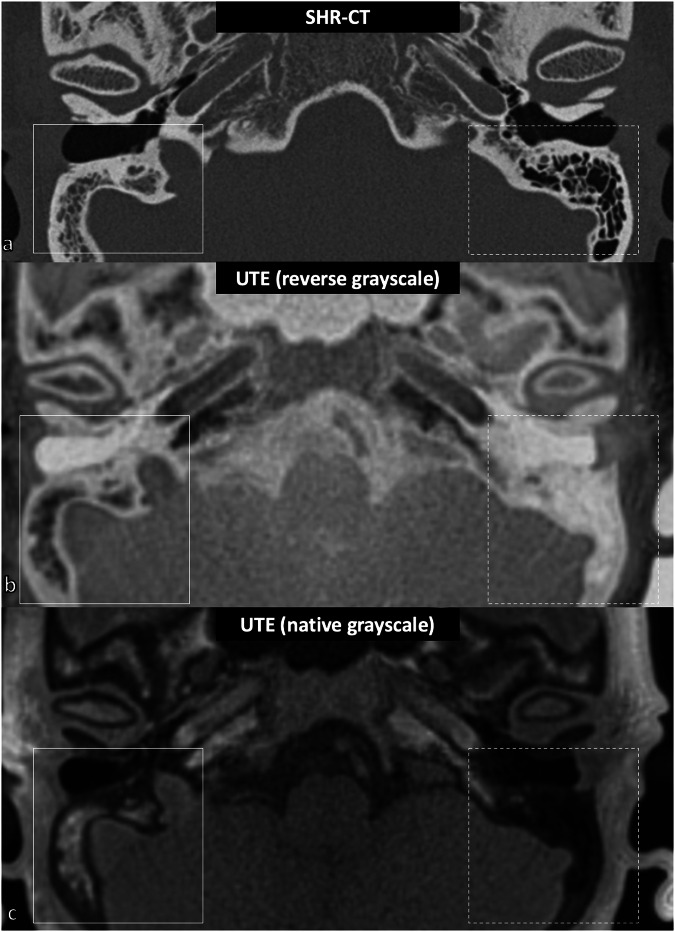

Results: The facial nerve was always clearly visible (score ≥ 2) in the MRI, NR-CT, and SHR-CT scans (p ≥ 0.621). However, the chorda tympani nerve (CTN) was clearly visualized in UTE, STARVIBE, and PETRA sequences in only 33% (2/6 specimens, p = 0.016), 50% (3/6 specimens, p = 0.038), and 83% (5/6 specimens, p = 0.017) of cases, respectively, whereas it was always clearly visualized in SHR and NR-CT (p = 0.426). The round window (RW) was never visualized in MRI sequences (p ≤ 0.010), whereas it was identified in all cases in SHR and NR-CT (p = 1.000). There was a strong correlation between measurements obtained from MRI and CT modalities (ICC ≥ 0.837).

Relevance statement: CT-like MRI sequences can image the anatomy of the facial recess and the length of the basal turn of the cochlea with similar accuracy as conventional CT, although they cannot image the round window.